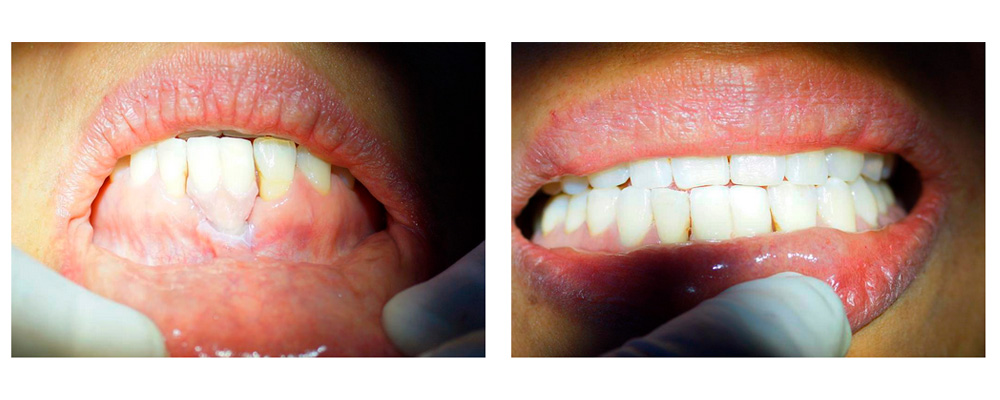

La figura 10 muestra la sonrisa al culminar el tratamiento y se puede comparar con la figura 1 al inicio del tratamiento. Se dictamina un pronóstico favorable.

Resultados y Conclusiones. Colocar un implante dental de titanio fuera de la guía de erupción dentara puede ser favorable analizando el caso clínico determinado. La colocación de implantes dentales de DSI que tienen superficie expansora en pacientes con baja calidad ósea pueden ser la mejor alternativa para el tratamiento indicado.